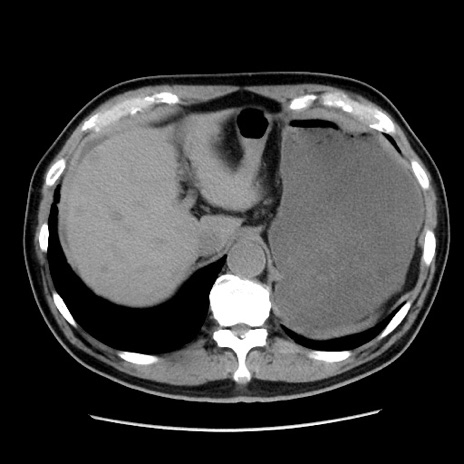

症例16(横断像)

【症例】 70歳代男性

【主訴】 腹痛、嘔吐

【現病歴】 約1ヶ月前より間欠的に腹痛と嘔吐あり、当院消化器内科を受診したところCTで多発する肝臓のLDAを指摘され、精査中であった。以降は消化器症状は安定していたが、2日前より嘔気と腹痛があり、同日より排便・排ガスが消失した。改善認めず、 本日、救急外来を受診した。

【既往歴】 大腸ポリープ切除後。

【身体所見】意識清明・会話良好、BT 36.3℃、BP 127/80mmHg、 P 80bpm、腹部:膨満あり、平坦・軟、上腹部正中および下腹部正中に圧痛あり、反跳痛なし、筋性防御なし。

【データ】WBC 7200、CRP 0.77